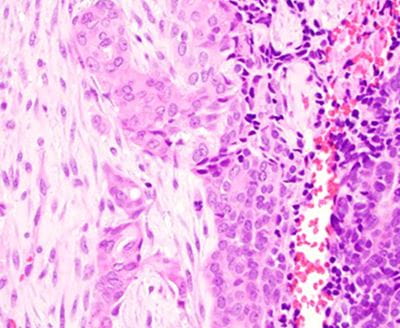

Microscopic findings

The tumor predominantly grows in the submucosal areas, forming cribriform nests, ductal structures, trabecular arrangements, or solid sheets. The tumor cells are basaloid with scant cytoplasm. Focal areas of squamous differentiation, characterized by eosinophilic cytoplasm, are observed. The overlying squamous mucosa exhibits high-grade dysplasia.